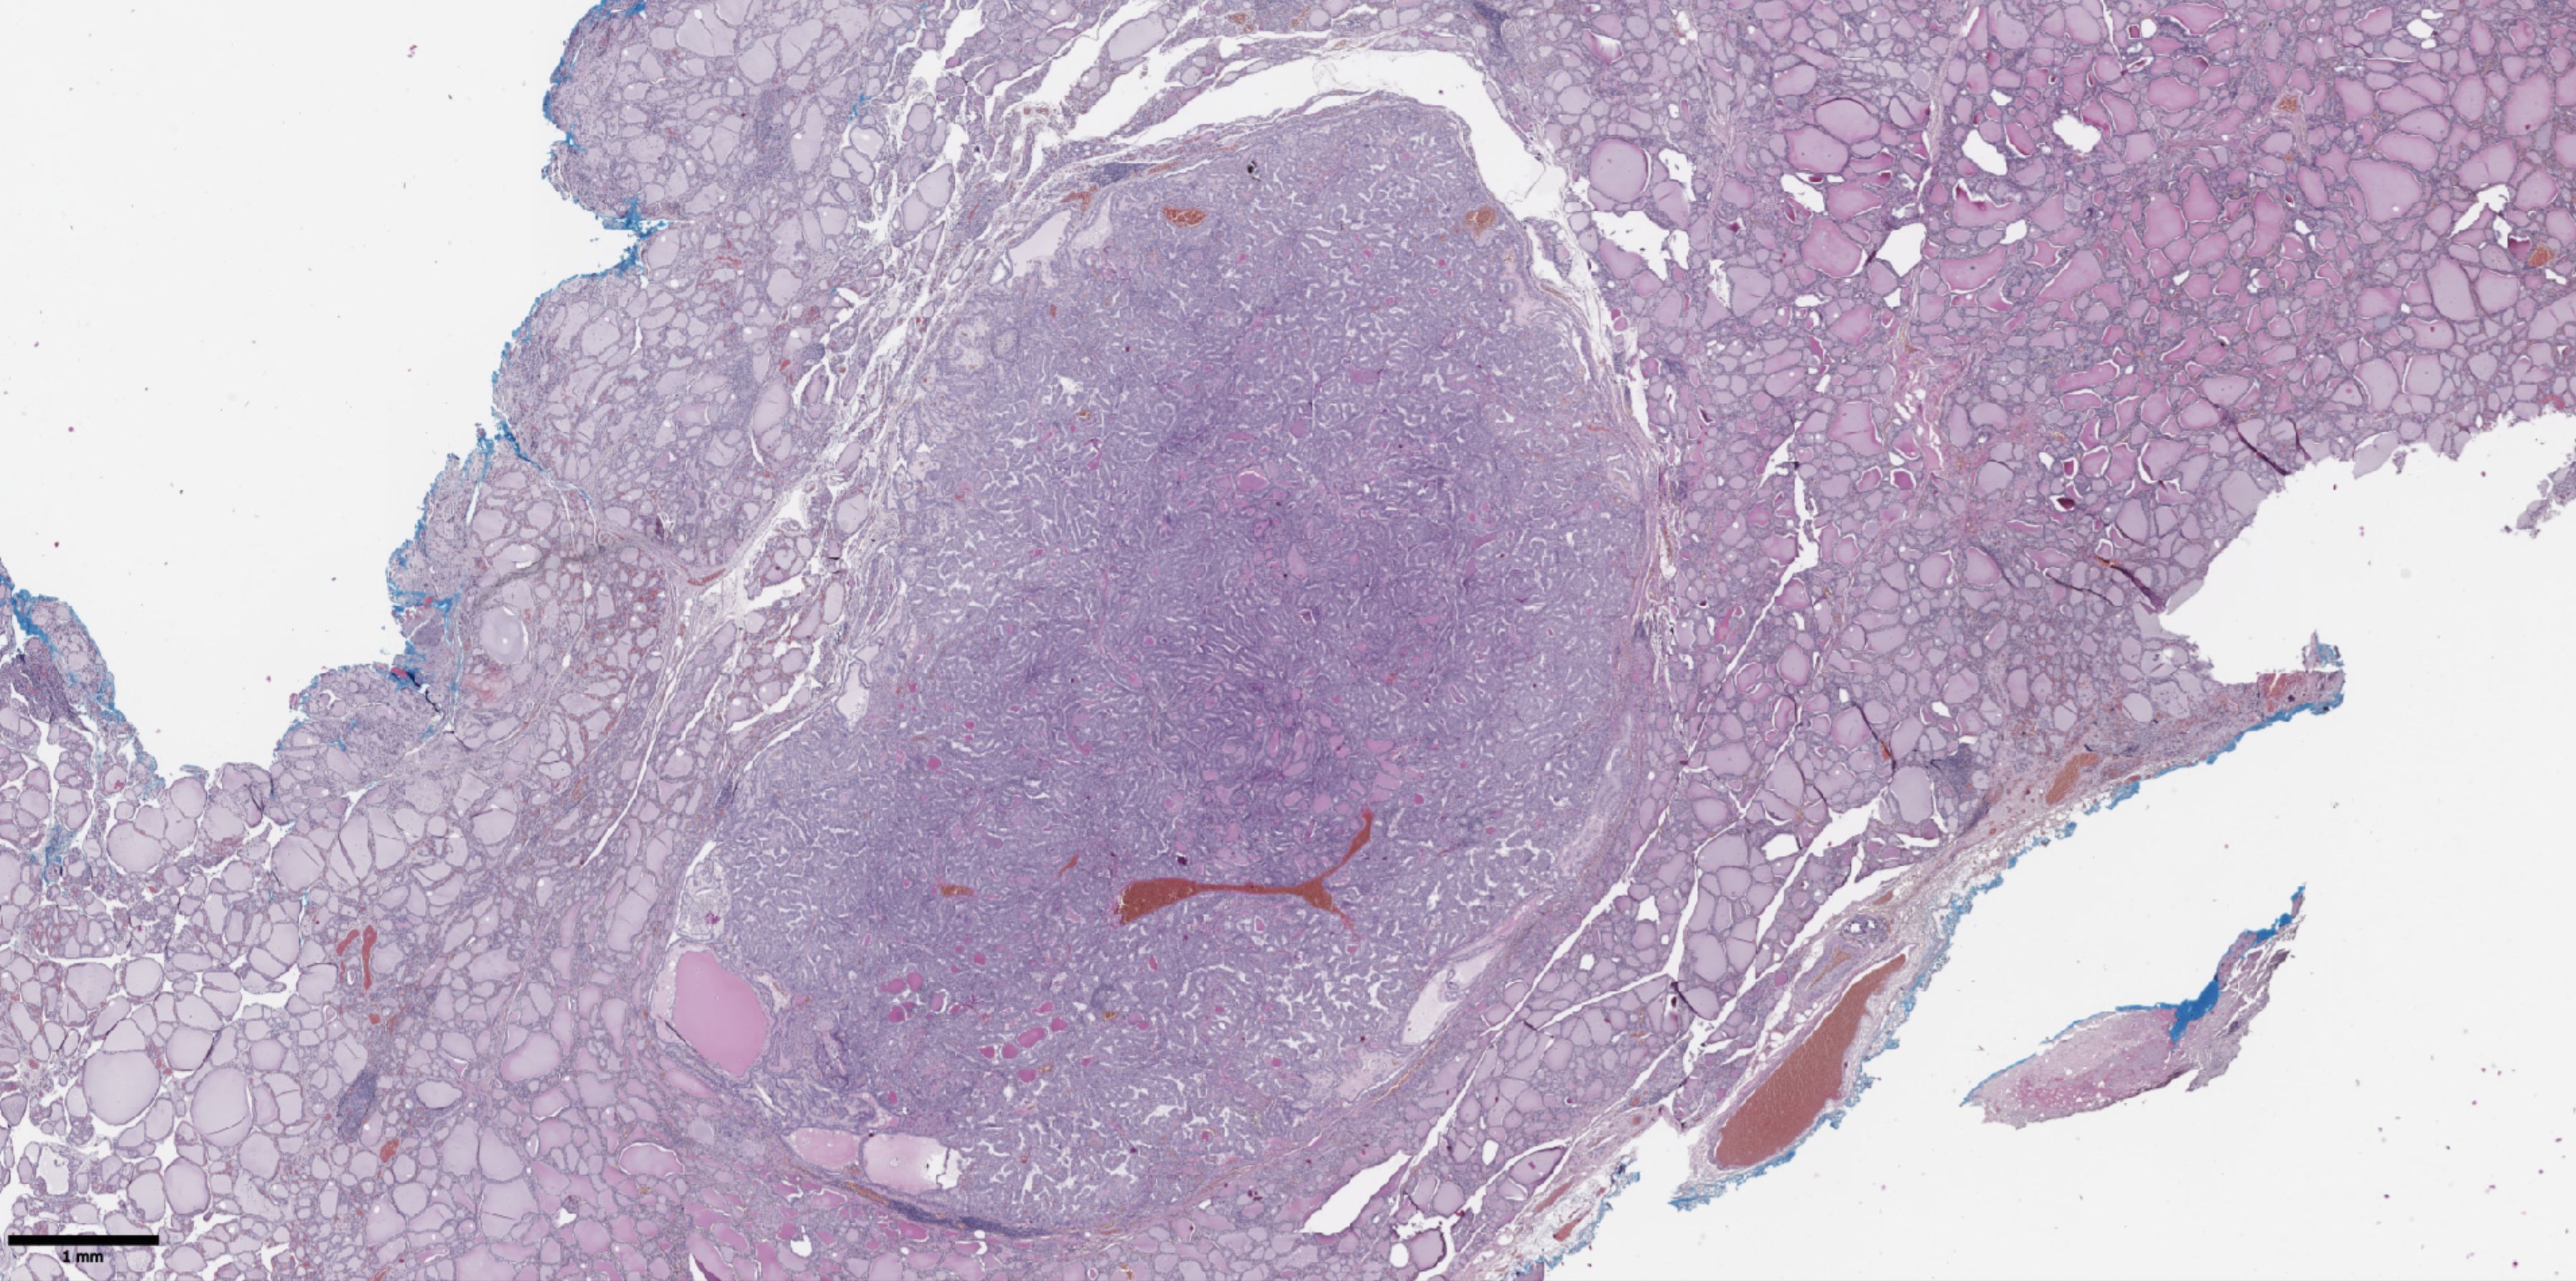

The groups were compared based on a number of tumor morphological features. The following were evaluated: the largest tumor node (Figure 1) and metastatic focus size (Figure 2), the histological subtype of papillary carcinoma according to the WHO classification (26), the presence of tall cell (Figure 3), Warthin-like, and squamous cell components in the tumor, foci of calcification and ossification in the tumor, a lymphocytic rim around the tumor node in the thyroid lobe tissue, apical vacuoles in tumor complexes, psammoma bodies in the tumor tissue (Figure 4) and in the thyroid tissue outside the tumor, the presence of a tumor capsule or its fragments, tumor “buds” (Figure 5), invasion of adipose tissue, perineural invasion, concomitant nodular thyroid diseases (tumor and non-tumor), and thyroiditis. Additionally, the following nuclear features of tumor cells were noted: angular contours, nuclear grooves, and intranuclear pseudoinclusions (Figure 6). Nucleoli in tumor cell nuclei were assessed using criteria partly adopted from the modified WHO/ISUP classification by S.A. Fuhrman for grading renal cell carcinomas (27), namely: the presence of nucleoli basophilic, visible but not prominent at ×100, or nucleoli conspicuous at ×100, basophilic, or nucleoli conspicuous at ×100, eosinophilic at ×400. Furthermore, the number of mitotic figures per 2 mm² of tumor tissue in “hot spots” and the presence of atypical mitotic figures were assessed. The degree of tumor fibrosis was visually graded as 0 (no fibrosis), 1 (fibrosis in less than 50% of the tumor node), or 2 (fibrosis in 50% or more of the tumor node) (Figure 7). A tumor “bud” was defined as a tumor complex no larger than 0.1 cm in diameter, located no more than 0.1 cm far from the tumor node, with one or more non-neoplastic thyroid follicles between them, which could not be reliably differentiated during routine histological examination between a tumor embolus in a vessel lumen (blood or lymphatic), an additional independent microfocus of tumor growth, or a tangential section of a tumor invasion area into adjacent thyroid tissue.

Figure 1. Histological image of papillary thyroid microcarcinoma. The tumor node is represented by papillary and follicular structures formed by cells with papillary nuclear features. Hematoxylin–eosin, х20.

Figure 2. Histological images of metastases in regional lymph nodes of papillary thyroid microcarcinoma. Most of the lymph node tissue is replaced by a tumor. Hematoxylin–eosin, х30.